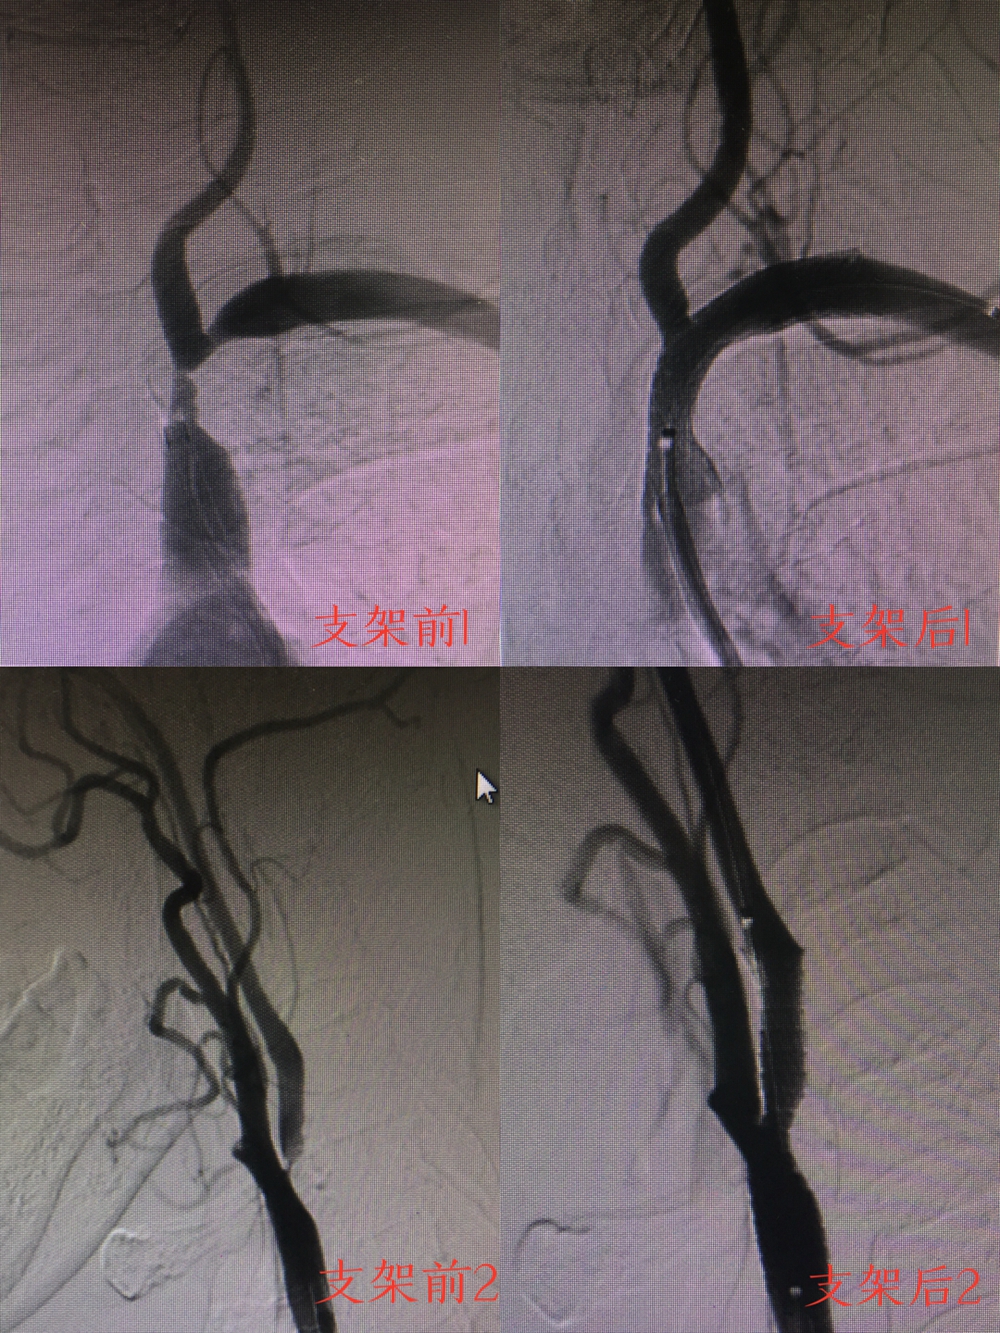

走介入步伐,追时代脉搏。近日,神经内科Ⅱ医疗团队在刘忠志主任的带领下,成功为两位患者进行了脑动脉支架置入手术。其中有一位患者的病情特点比较复杂,患者半年来反复出现阵发性头痛,四肢乏力,肢体麻木,曾反复在院外治疗,效果不佳。且既往病史较多,患有高血压、冠心病、腔隙性脑梗塞等多种慢性病史。该患者颈动脉及脑血管造影示:左境内动脉起始部狭窄约95%。于8月 29日上午在神经内科的介入团队协作下成功完成了颈内动脉支架植入术。至此,神经内科的介入治疗紧跟时代发展脉搏,不断快步向前。